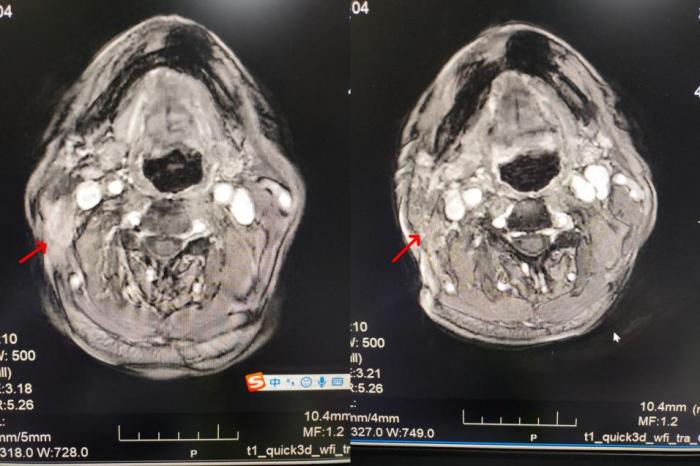

接诊后,肿瘤二科主任曹苏娟带领团队对李爷爷的病情进行了全面评估。“患者颈部的肿块紧邻咽喉部位,若采用传统放疗,极易损伤咽喉黏膜与唾液腺,进而引发咽喉疼痛、吞咽困难等不良反应,不仅会影响正常进食、导致生活质量大幅下降,甚至可能让患者无法耐受完整疗程。” 曹苏娟主任一语道破治疗难点。

针对李爷爷的特殊病情、年龄等因素,科室医护团队迅速展开研讨,为其量身定制了TOMO放疗的个性化治疗方案。与传统放疗相比,TOMO放疗犹如为射线配备了“精准导航”,能够对肿瘤病灶实施精准靶向“打击”,同时最大限度保护周边的唾液腺、咽喉黏膜等正常组织,显著提升了患者的治疗耐受性。